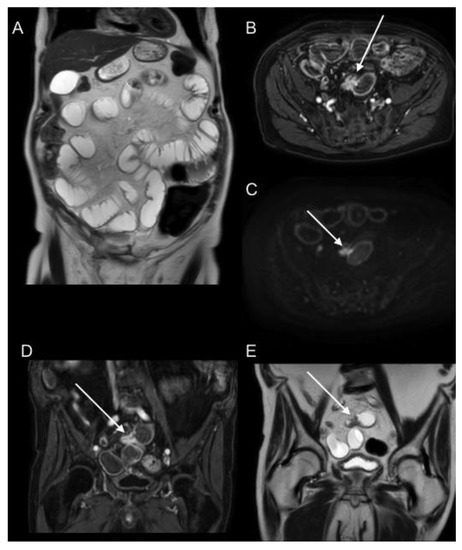

- De Vuysere, S.; Vandecaveye, V.; De Bruecker, Y.; Carton, S.; Vermeiren, K.; Tollens, T.; De Keyzer, F.; Dresen, R.C. Accuracy of whole-body diffusion-weighted MRI (WB-DWI/MRI) in diagnosis, staging and follow-up of gastric cancer, in comparison to CT: A pilot study. BMC Med. Imaging 2021, 21, 1–9. [Google Scholar] [CrossRef] [PubMed]